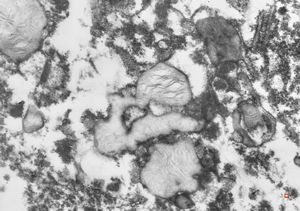

M,5y. | mitochondrial changes - Reye hepatocerebral syndrome